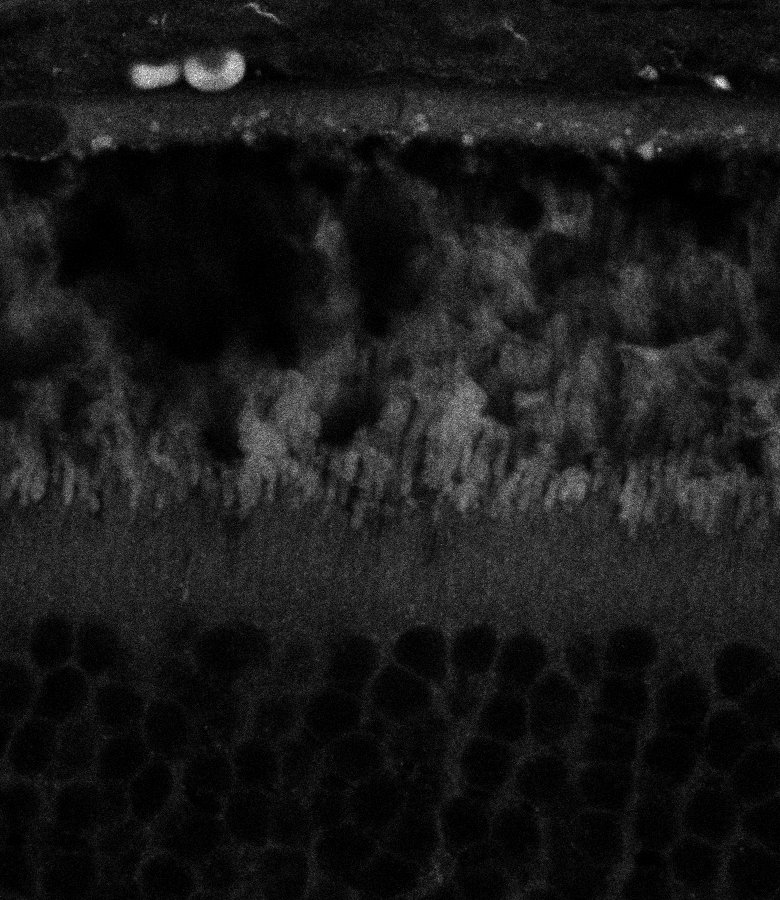

Healthy Choroid

Unhealthy Choroid